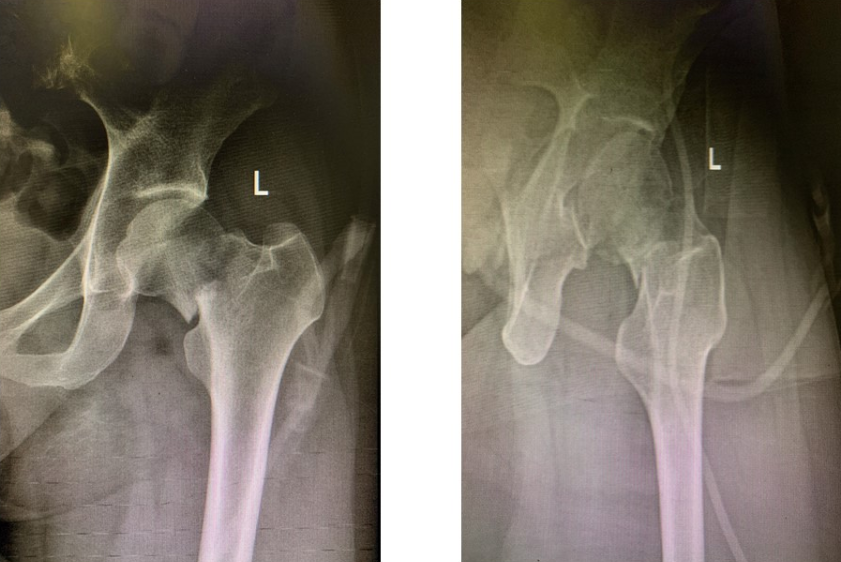

43岁的龚女士现居云南,因外伤导致左股骨颈头下型骨折,且为移位最严重的Garden IV型,股骨头坏死率可能高达40%,当地医院建议她接受髋关节置换手术。尚年轻的她心怀希望四处打听,从朋友那里得知中南大学湘雅三医院骨科可以开展中青年患者保髋手术,便驱车1400多公里,慕名找到中南大学湘雅三医院创伤骨科。接诊后,骨科兼关节外科主任吴松教授、创伤骨科主任罗令教授为远道而来的龚女士进行了会诊,与她进行了深度交流,综合考虑患者年龄、严重股骨头骨折后坏死率高等特点,制定了一期采用创新性旋髂深血管蒂髂骨瓣移植技术来修复股骨颈骨折、预防股骨头坏死的方法。

罗令教授介绍,对于年轻的股骨颈骨折(Pauwells III型,Garden IV型)患者,股骨头预期坏死率高,带旋髂深血管蒂髂骨瓣移植预防股骨头坏死是一种很有效的治疗方法,但经典手术方式存在创伤大、血管已受卡压从而影响髂骨瓣存活等缺点。湘雅三医院创伤骨科对原有术式进行了多项改良,新术式降低了移植血管受压可能性,移植后的髂骨瓣成活率更高,完整地保留了腹股沟结构与功能,还保留了髂骨的外形,供区损伤更小,更符合目前微创、美学的理念。5年来,创伤骨科已成功为20名股骨颈骨折中青年患者开展了保髋手术,股骨头坏死率由40%降低至10%。